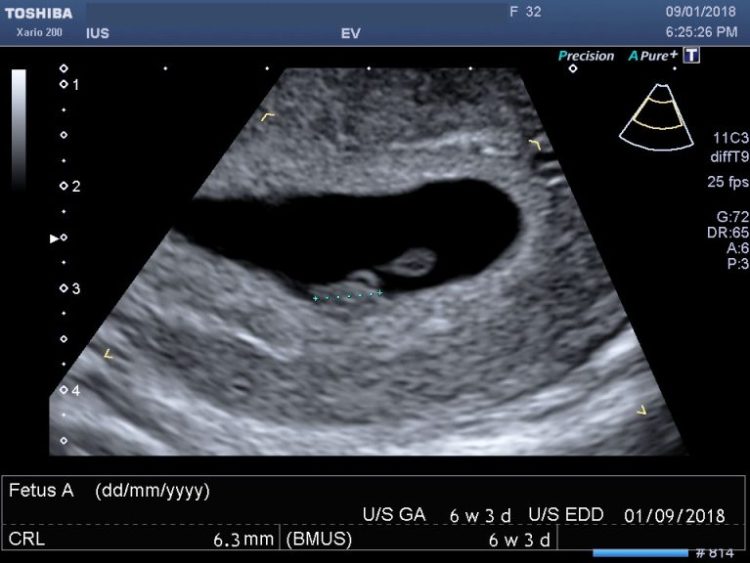

One major perk is the high-quality imaging equipment that many private clinics use. Even while the NHS uses high-quality equipment, private clinics typically have the most up-to-date technology, which results in pictures that are crisper and more detailed. With this enhanced clarity, parents can have a more holistic view of their baby’s developmental progress. Thanks to technological advancements, parents can now have a more lifelike and immersive encounter with their unborn child through 3D and 4D scans. In addition to providing confidence, these pictures will last a lifetime and be treasured by families. The capacity to record high-definition footage and photos provide concrete evidence of this unique adventure, making it all the more meaningful.